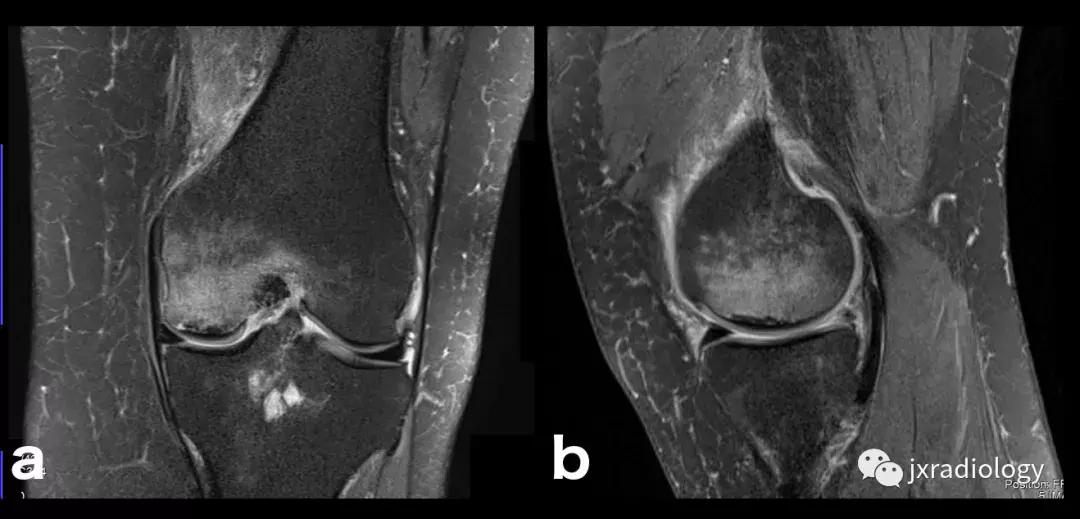

图20:患有血红蛋白病的患者(例如镰状细胞性贫血),在这种情况下,容易发生继发于毛细血管阻塞的骨坏死。这种阻塞导致毛细血管静水压升高,造成水敏性序列中低信号骨梗死周围的高信号水肿。这是充血性骨髓水肿的一个例子(由于骨髓空间毛细血管床液体流出受损)。该患者还表现出广泛的红骨髓转化,如T1-WI中的骨髓信号所示(远低于周围脂肪组织并略高于肌肉组织)和DP-FS-WI(未完全饱和,保持略高信号)( a:冠状面DP-FS-WI; b:冠状面T1-WI; c:轴向T1-WI; d:矢状面DP-FS-WI)。

图21:这名患者的炎症性关节炎表现为围绕内侧股 - 胫室侵蚀性改变的骨髓水肿。它是血管源性骨髓水肿的一个例子(继发于血液和血清传递至骨髓空间毛细血管床)(a,b:冠状T1-WI和PD-FS-WI)。